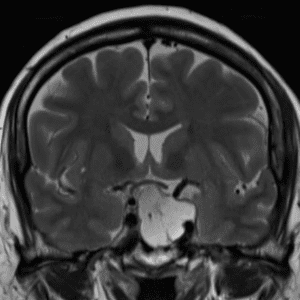

Case #43

Secondary CNS lymphoma